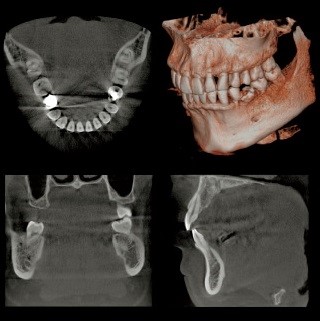

歯の状態や、歯を支える歯槽骨の状態、骨吸収の範囲と程度を検査します。

CT検査は立体的に歯槽骨の状態を診ることができるので、通常のレントゲンで顕著な骨吸収が診られた場合に撮影します。

自由診療の検査費用となります

診査、分析に基づき、診断いたします

治療はそれ以降となります